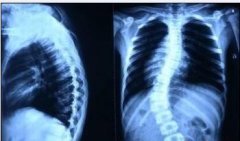

强直性脊柱炎的危害对身体的造成的后果非常严重,对此,阿坝强直医院专家将对强直性脊柱炎的危害进行详细的介绍,以便患者早日恢复健康。 强直性脊柱炎的病变表现主要有:腰椎病变、颈椎病变、胸椎病变、周围关节病变、骶髂关节炎、心脏